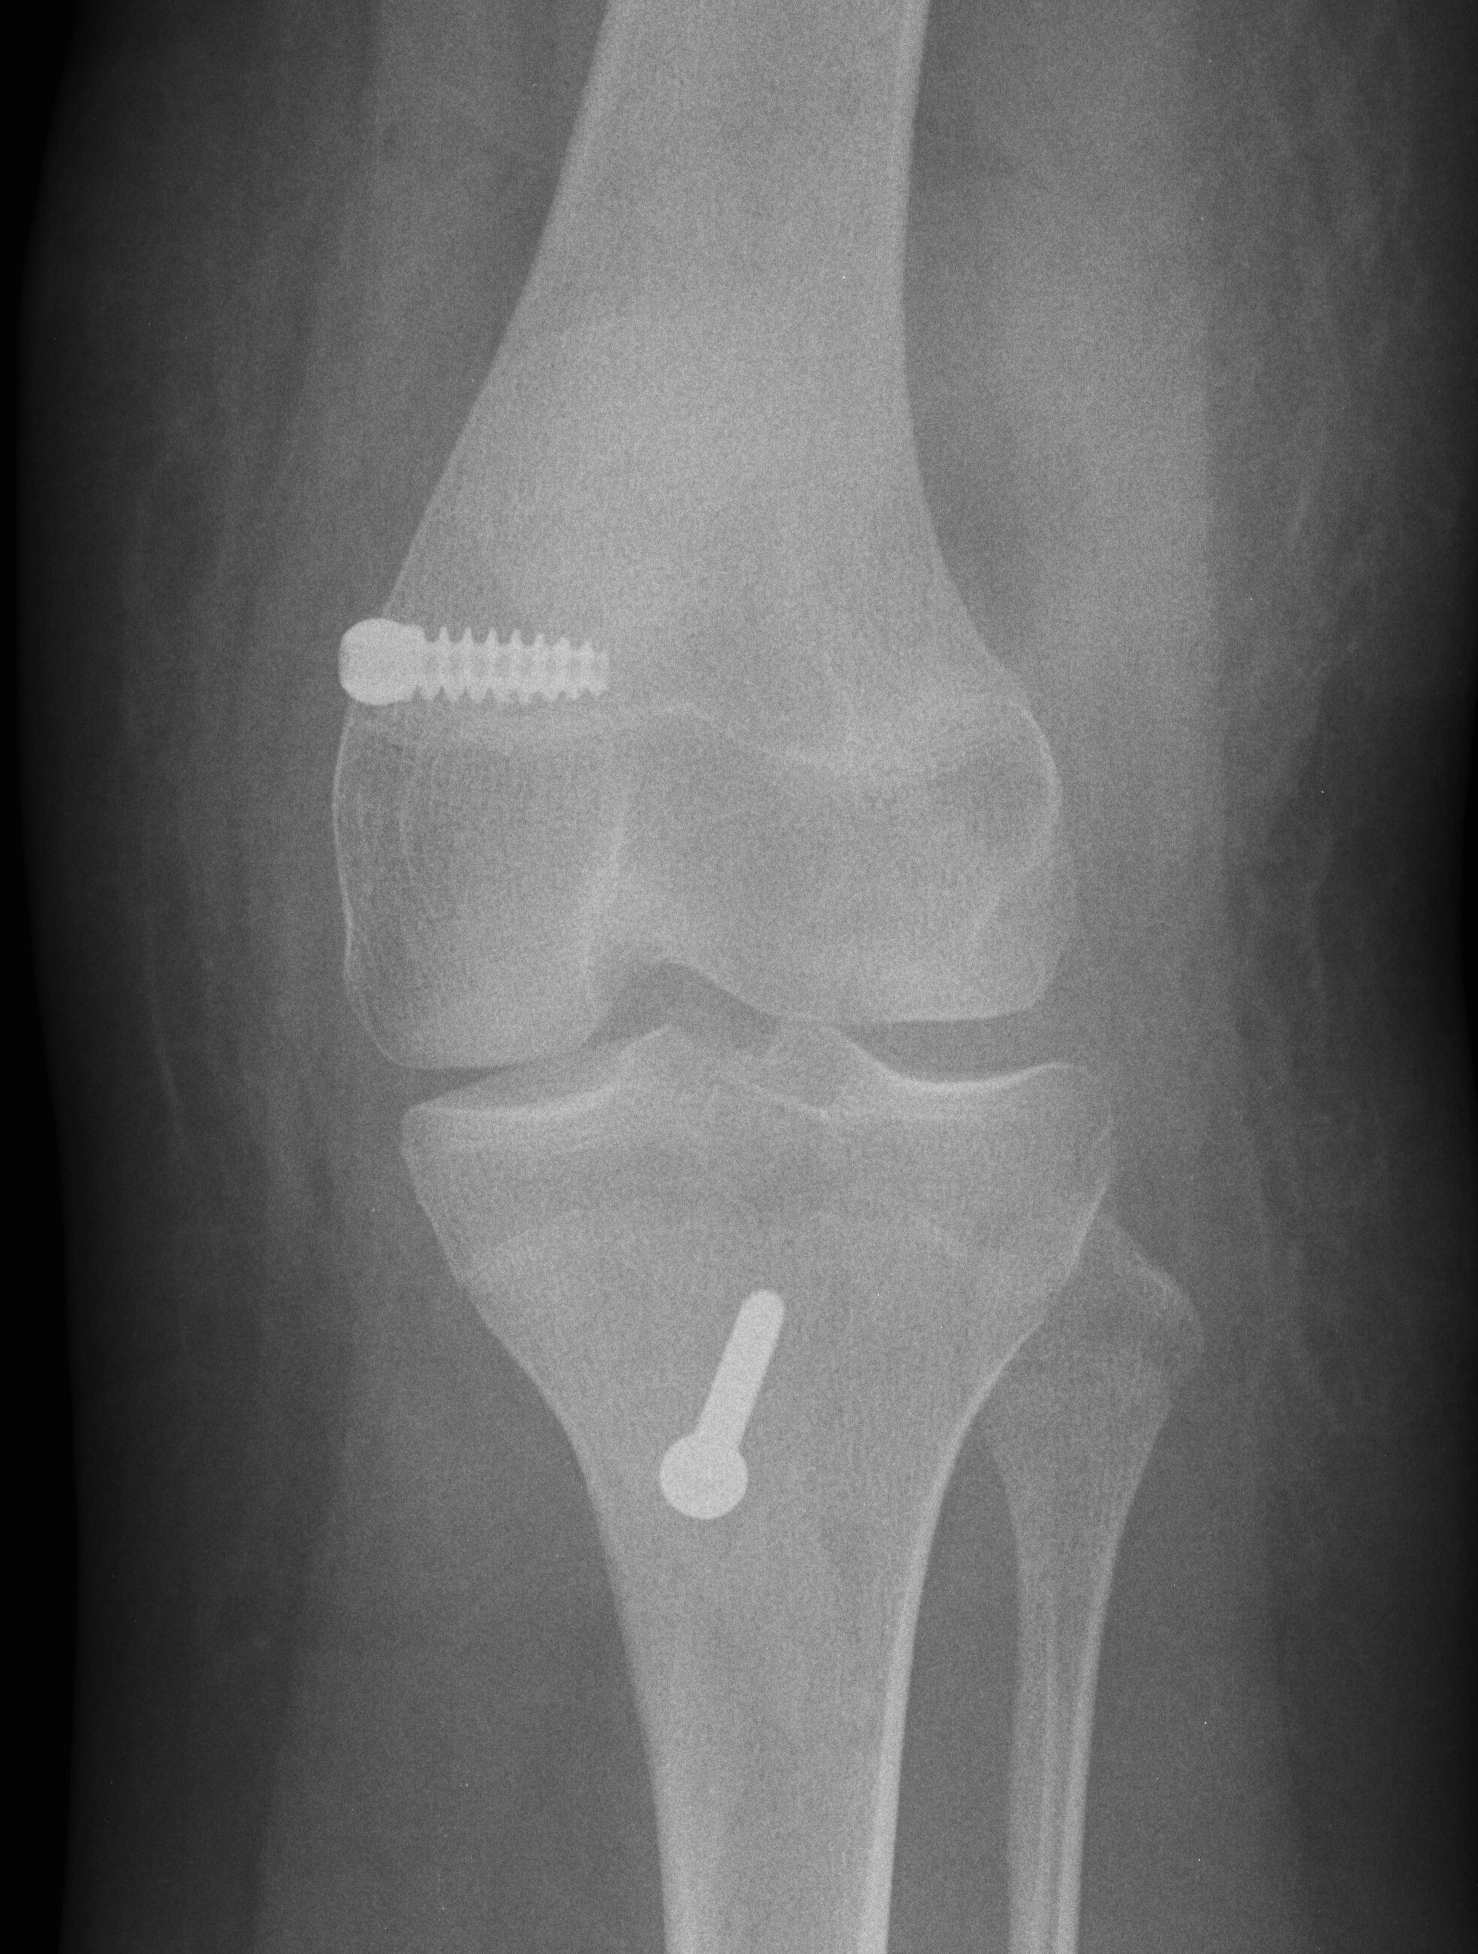

Xray 2

Finding Schottles Point